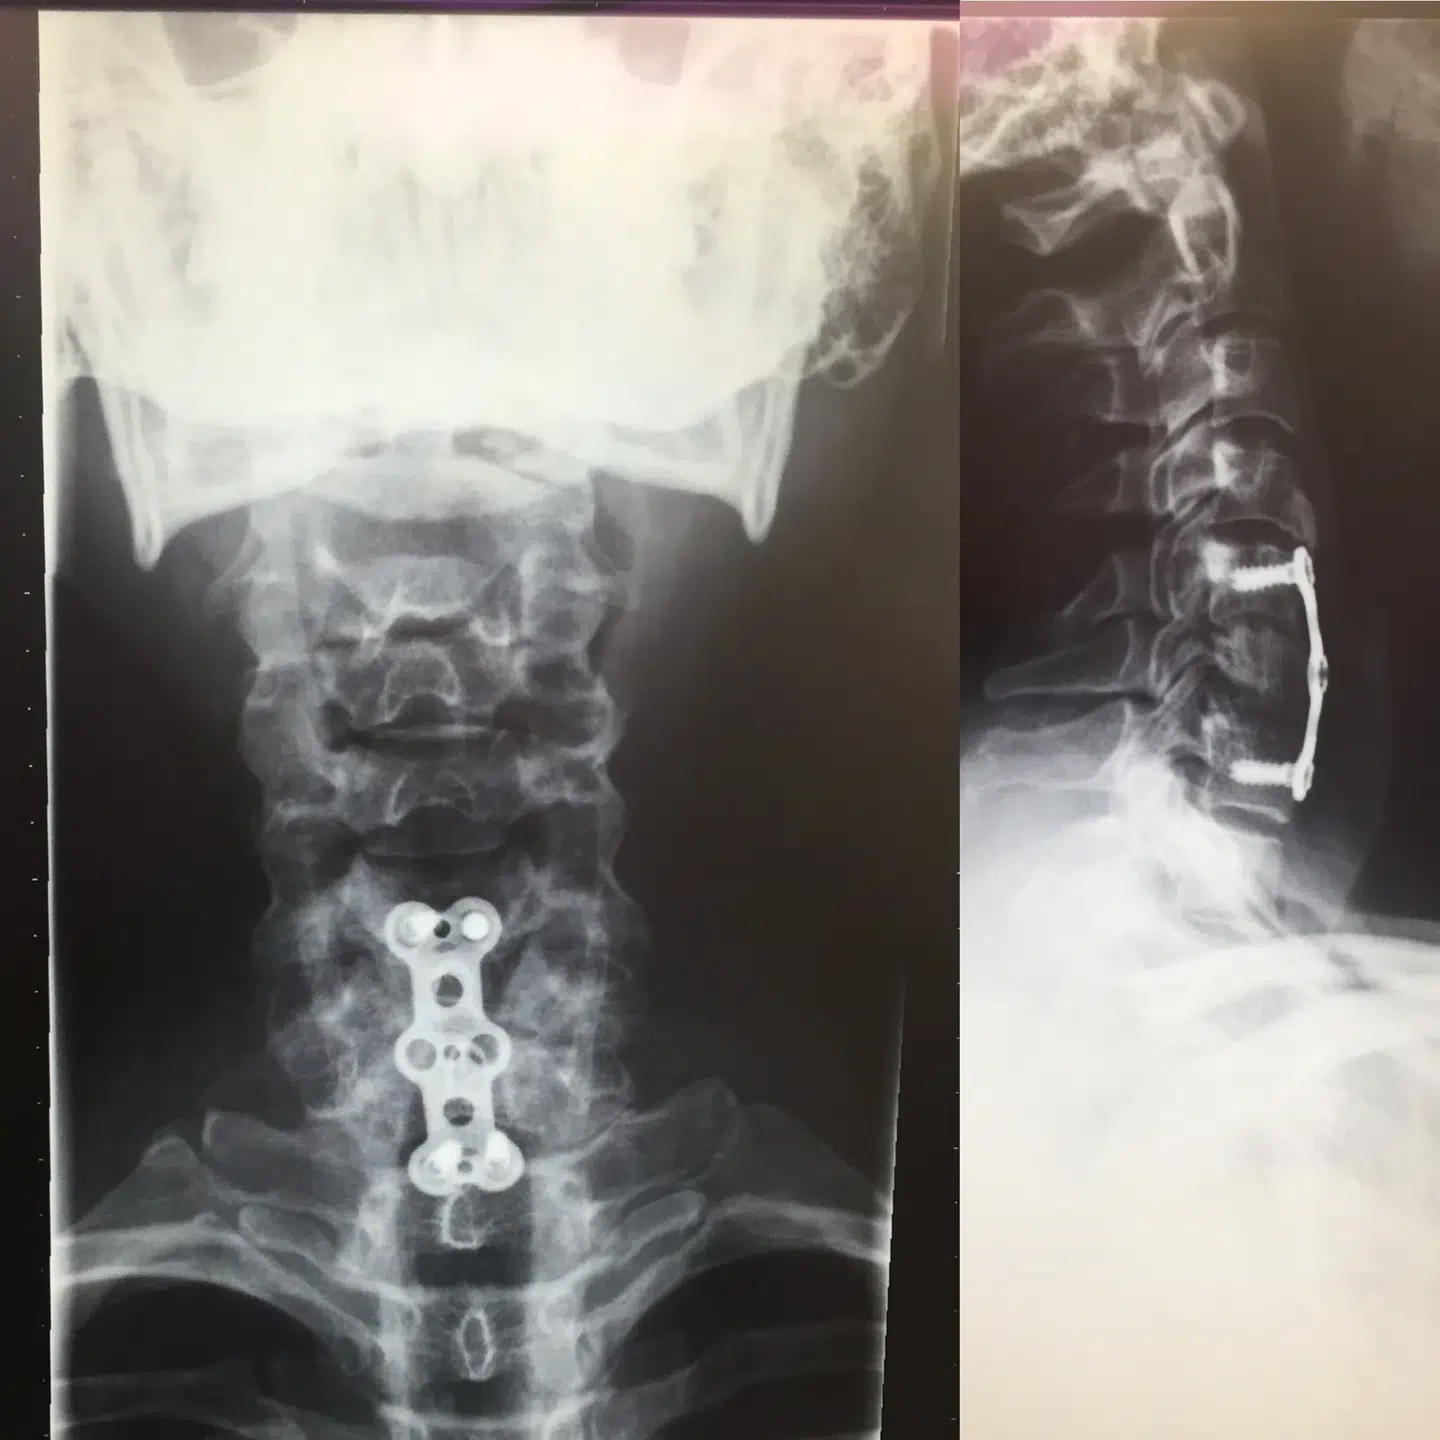

På forsiden af Jesper Vollmers hals sidder der et ar. Det var dér, kirurgerne åbnede op for at kunne samle femte, sjette og syvende nakkehvirvel med et titanium-implantat.

»Det ligner en vingummibamse,« griner han og viser røntgenbilledet.